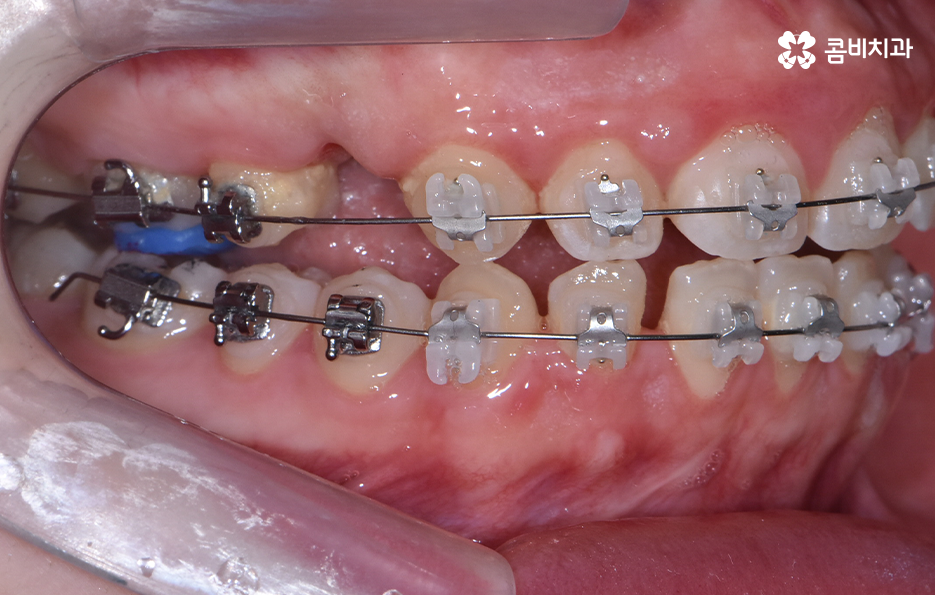

다음으로 교정 장치를 부착한 상태를 보시면 윗니는 양쪽의 치아 하나씩을 발치하였고 아랫니는 치아가 벌어져 있는 공간이 있기 때문에 발치 없이 교정을 진행했어요

앞니가 일반적인 경우보다 다소 돌출되어 있던 상태이기 때문에 앞니의 발치 교정을 통해 가지런한 치열 뿐 아니라 얼굴형이 변화하여 외모적인 개선도 기대할 수 있었어요. 치아교정의 목적에 있어서 치열 뿐 아니라 얼굴변화를 주된 목적으로 치과에 방문하는 경우도 많이 있는데요.

기본적으로 치아교정은 보다 가지런한 치열로 인해 자신감 있게 웃는 얼굴 만으로도 밝은 인상을 주는 효과가 있지만 치아의 이동이 많을수록 얼굴의 실질적 변화가 더 크기 때문에 치아교정에 대한 니즈가 치열 뿐 아니라 얼굴형에 더 초점을 두는 경우에는 발치 여부를 고려하는 경우도 종종 있어요

다만 치료 계획 상의 발치 여부나 구체적인 치료 방법 등은 3D CT 등을 활용하여 치아와 골격, 얼굴형을 종합적으로 판단하여 1:1 맞춤형으로 진행되고 있다는 점을 먼저 알아두시길 바라며 각 개인에 따라 적합한 치료 계획도 달라지고 있다는 점에서 교정 치료의 케이스는 참고 정도로만 하시고 자신에게 맞는 방법은 정밀검진과 교정 전문의와의 충분한 상담을 통해 판단하실 필요가 있어요